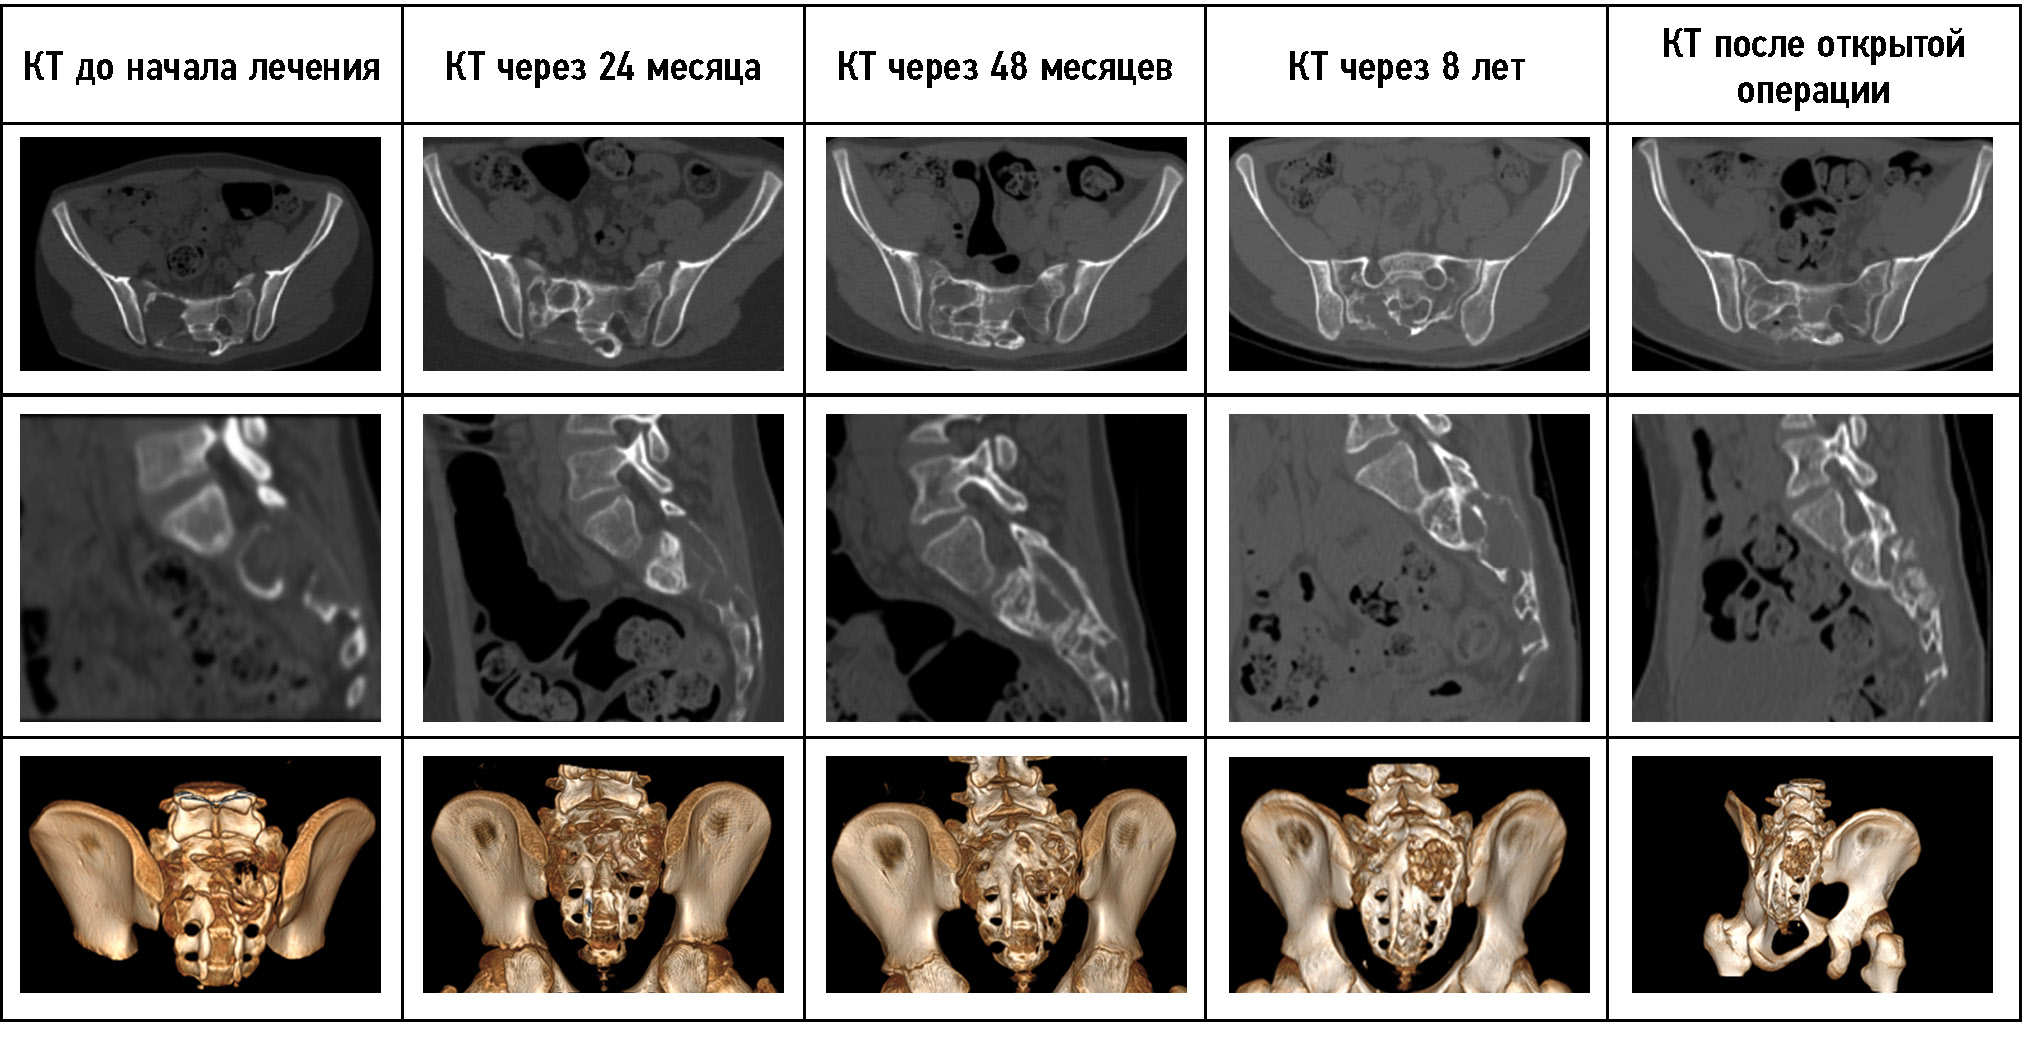

На момент первой госпитализации возраст пациента составлял 16 лет. По месту жительства выявлено новообразование крестца, выполнена открытая биопсия, гистологически поставлен диагноз — аневризмальная костная киста крестца. При первом поступлении в отделение детской костной патологии и подростковой ортопедии предъявлял жалобы на боль в области крестца до 7 баллов по ВАШ, боль иррадиировала в правую нижнюю конечность до пятки, также отмечал периодическую боль при акте дефекации, запоры. Вышеуказанные жалобы беспокоили с ноября 2021 г. с постепенным ухудшением. Представлены МРТ пациента при первом поступлении в стационар (рис. 2). По данным лучевых методов исследования отмечаются лизис костной ткани в области опухоли, компрессия невральных структур, отдавливание тазовых органов. Оболочка опухоли представлена её мягкотканным компонентом без признаков окостенения. Пункционное лечение начато в апреле 2020 г. При первичной пункции давление в опухоли составило 510 мм вод. ст., кровопотеря — 150 мл. На момент третьей госпитализации (после 4 пункций и 3 месяцев с начала лечения) жалобы на боль и неврологическая симптоматика регрессировали. Можно наблюдать признаки частичной оссификации оболочек опухоли, выстраивание костных мостиков в полости кисты через один год (после 12 пункций) с начала лечения пациента. На 13-й пункции давление менее 120 мм вод. ст., кровопотеря менее 50 мл. В связи со снижением активности принято решение о частичной резекции задней стенки опухоли и дренировании глубоких отделов АКК. Через 6 месяцев введён костнопластический материал Коллап-Ан в полость кисты. На КТ-исследовании через один год после открытой частичной резекции задней стенки опухоли и дренирования глубоких отделов АКК и через 6 месяцев после пункционного введения костнопластического материала определяется постепенное восстановление костной ткани крестца, полное окостенение оболочек кисты. Как и в большинстве случаев при восстановлении костных структур, отмечается формирование просвета позвоночного канала и анатомии крестцовых отверстий по принципам памяти костной формы, что отчётливо визуализируется на контрольных КТ-исследованиях. При динамическом наблюдении и на момент повторных госпитализаций пациент отмечал полный регресс болевого синдрома и неврологической симптоматики уже после четвёртой манипуляции. Данных о продолженном росте патологического процесса получено не было. Пациент проходит этапное пункционное лечение. Динамика КТ-исследования пациента 1 представлена на рис. 3.

Рис. 3. КТ-динамика лечения пациента 1. На представленных КТ-снимках можно наблюдать уменьшение объёмов кисты, формирование собственной костной ткани. КТ-исследование через 12 месяцев выполнено перед открытой операцией в объёме частичной резекции задней стенки опухоли и дренирования глубоких отделов аневризмальной костной кисты.

Fig. 3. The CT scans of the patient’s treatment show a decrease in the cyst volume and the formation of bone tissue. A follow-up CT scan was done 12 months before the open surgery to partially remove the posterior wall of the tumor and drain the deep sections of the aneurysmal bone cyst.

Рис. 7. КТ-динамика лечения пациента 3. На КТ через 8 лет от начала лечения определяется формирование резидуальной полости.

Fig. 7. The CT-dynamics of the patient’s treatment № 3. After 8 years of treatment, a residual cavity was determined on CT.

Показатель | Slice Thickness, мм | V, см3 | Max HU | Min HU | Avg HU |

До начала лечения | 1,25 | 19,9 | 740 | -79 | 70,2 |

КТ через 24 месяца | 1,25 | 27,6 | 947 | -99 | 173,8 |

КТ через 48 месяцев | 1,25 | 43,2 | 1065 | -75 | 188,7 |

КТ через 8 лет | 1,25 | 45 | 1395 | -173 | 200,2 |

КТ после открытой операции | 1,25 | 46,1 | 1384 | -126 | 249,7 |